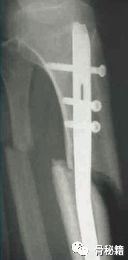

轻微粉碎的病例,多发伤患者,皮肤条件不好,不敢切开,先植入两枚阻挡钉,后方一个,侧方一个,进针之后,发现导针穿出后方……

说明这后方的阻挡钉没设计好,然后又在下方植入了一个阻挡克氏针